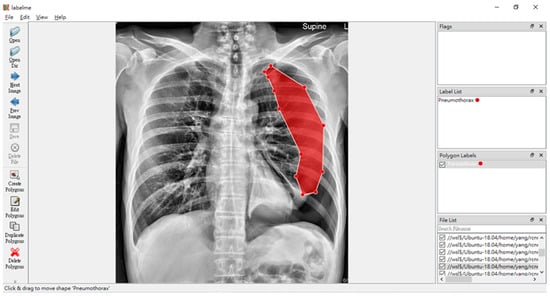

This research project aims to build a usable X-ray images lung disease detection system. Our dataset consists of over 8000 X-ray images, with more than 1000 of them from pneumothorax patients. In this project, we utilized a software called LabelMe [24], as shown in Figure 1. LabelMe annotation project is a standard software that is used to annotate interest segments from a given image and to classify those said segmented images.

Figure 1.

LabelMe in action on annotating pneumothorax, with the red shadow marking the ground truth of the affected area of the pneumothorax disease.